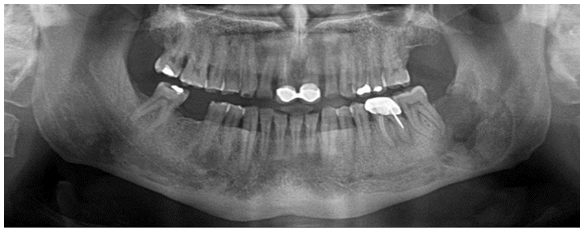

A 55-years-old male presented to our department, with a chief complain of severe pain in the mandibular left molar region. Past medical and dental history revealed that approximately one year ago the patient complained of pain at the same region, where defective endodontic treatment was performed on tooth #36 in a private dental clinic but no permanent relief was obtained. No trauma history was reported. On extra oral inspection, there was a swelling on the lower left side. Intraoral examination showed obliteration of the left labial vestibule compared to the right premolar molar area. Teeth #36-37 showed no pain on percussion. Absence of the wisdom tooth #38 was noticed. The panoramic examination revealed a well-defined, corticated unilocular radiolucent area associated with an inverted tooth #38, located near the angle of the mandible, occupying the whole height of the ramus from the upper border of the mandible till the lower border, with a marked thinning of the borders. The inferior alveolar canal (IAC) is remarkably non visible at the region of the lesion (Figure 1).

Figure 1 Pre-operative panoramic x-ray showing a well-defined unilocular radiolucency associated with tooth #38, near the angle of the mandible.